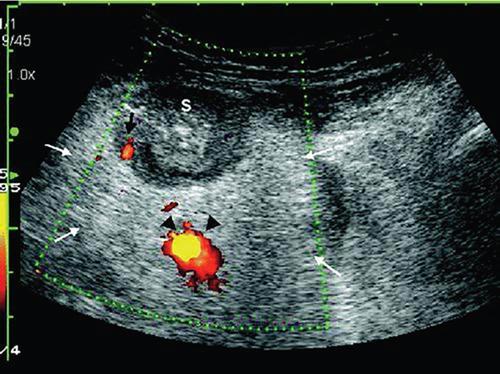

Ultrasonography (USG)